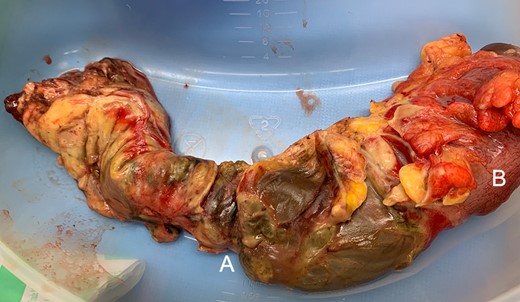

An exploratory laparotomy demonstrated the entire length of the rectum (from the anorectal junction to sigmoid) was necrotic with several points of perforation (Fig. 4), thus an ultra-low anterior resection was performed. An omental wrap was placed into the remaining pelvic defect and an end colostomy was fashioned from the remaining sigmoid colon. Significantly, there appeared to be no macroscopic evidence of disease to the remaining colon and small bowel. He was admitted to the ICU post-operatively and was gradually weaned from ionotropic support and ventilation, as he also overcame his comorbid aspiration pneumonia. He completed seven days of IV Piperacillin and Tazobactam as well as IV stress doses of hydrocortisone.

(A) Rectal gangrene with multiple sites of perforation. (B) Healthy rectosigmoid at proximal resection margin.